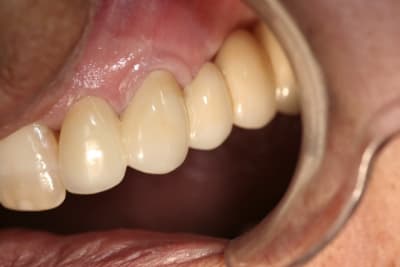

Img 3997 dk8k6g - Eugenol

Img 0426 jmyxaz - Eugenol

Img 5364 apxucc - Eugenol

mg 7102 nax8qq - Eugenol

mg 6276 umegd9 - Eugenol

mg 6424 aeia7y - Eugenol

mg 7430 nqcynh - Eugenol

Greuet franck 1965 04 02 x 2012 12 10 17 01 26 3 cvkaam - Eugenol

Greuet franck 1965 04 02 x 2012 12 18 09 40 50 3 lu0lwd - Eugenol

Greuet franck 1965 04 02 x 2012 12 18 11 08 55 3 iykklo - Eugenol

mg 6901 jfyxlf - Eugenol

mg 7355 ktalef - Eugenol

mg 7359 u1bpvu - Eugenol

mg 6411 byidhl - Eugenol

mg 7309 zwaijz - Eugenol

mg 7314 o38j8u - Eugenol

01/03/2013 à 18h27

c'est du beau travail jumpingjack !